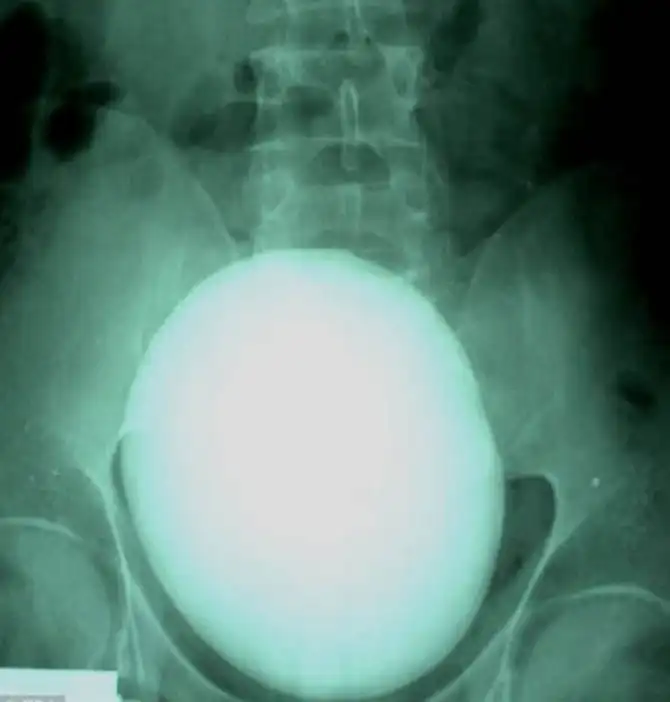

Вот такой вот 15-сантиметровый камень в почках весом 1,1 килограмм удалили пациенту из Венгрии.